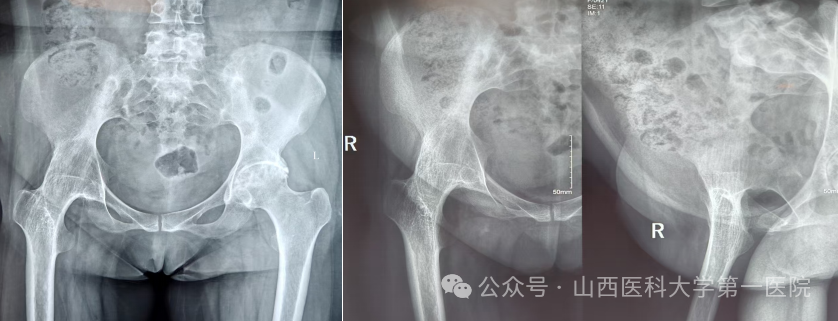

一名42岁的强直性脊柱炎患者,多年来饱受病痛折磨。随着病情进展,双侧髋关节逐渐“锈死”,无法弯腰、下蹲,甚至连坐下都成了奢望——吃饭只能站着,休息只能躺着,生活自理能力几乎丧失。接诊后,骨科杨自权主任团队对患者进行全面检查,发现患者不仅脊柱强直呈“板状腰”,双侧髋关节出现严重融合,而且双膝、双踝关节功能明显下降,手术难度极大。

针对患者复杂病情,科室组织多学科讨论。为实现从“站坐难安”到“稳步前行”,杨自权主任团队决定先为患者实施“右侧人工全髋关节置换术”。术中,团队凭借精湛技术,精准处理强直融合的关节结构,在保护周围神经血管的同时,成功植入新的人工关节假体。